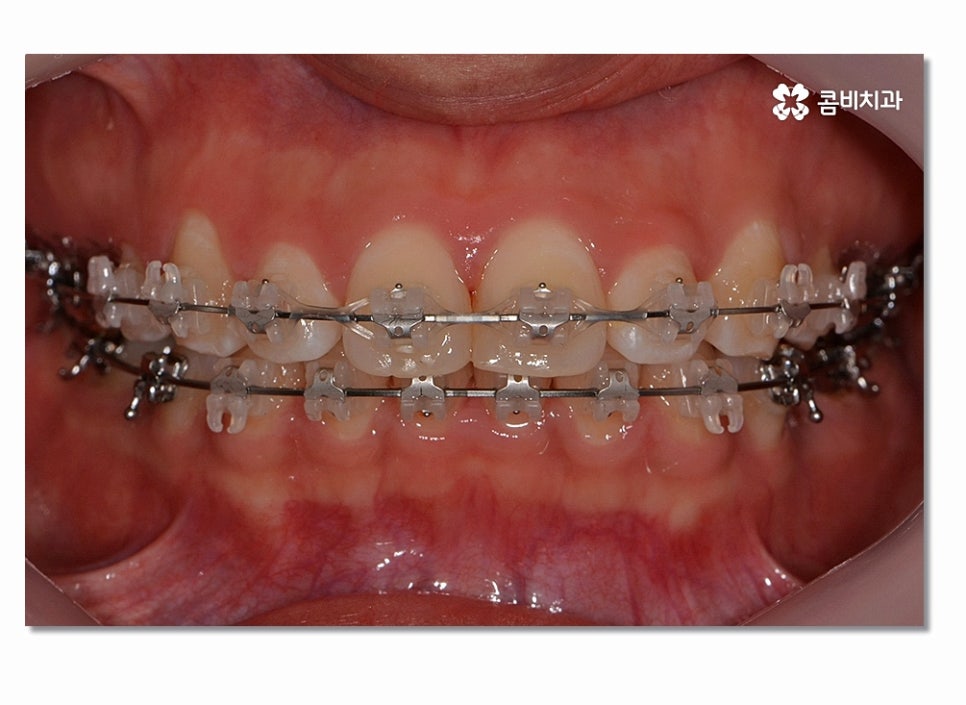

치아교정을 위해서는 치아가 이동할 수 있는 공간이 충분히 확보되어야 하며

돌출입치아교정의 경우 치아가 전방으로 뻐드러진 상태를

후방으로 이동시켜야 하기 때문에 원하는 결과를 위해서 필요에 의해

발치가 진행되는 경우도 많다고 볼 수 있어요.

일반적으로 작은 어금니를 발치하게 되는 이유라면 전체적인

악궁 크기에 맞게 치아를 이동시킬 공간 확보의 의미가 크며

돌출입치아교정이 시작되면 이처럼 전방으로 뻐드러진

앞니를 시간이 지남에 따라서 후방으로 이동시키면서 돌출입이

점점 개선되며 이러한 치열의 변화는 교합도 잘 맞물리도록

신경 써야 하며 얼굴 변화에 대한 부분까지 잘 생각해야 할 수 있어요.

위 사진을 보시면 치아교정 과정을 통해서 치열의 가지런함은 물론이며

측면에서 보더라도 돌출입이 많이 개선된 것을 느낄 수 있을 거예요.